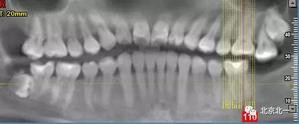

病例資料:一般情況,患者女性,28歲, 主訴:要求拔右側下頜智齒,檢查:右側下頜第三磨牙未見萌出, 拍片如圖。

圖一:CBCT顯示右側下頜水平骨埋伏牙,牙冠距離下牙槽神經管接近。

圖二:自帶的CBCT顯示下牙槽神經管貼著智齒走形。